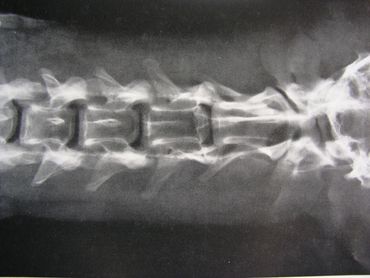

The spinal column is made up of four major vertebral regions: cervical (neck), thoracic (mid back), lumbar (low back) and sacral (pelvic). Dogs have seven cervical, thirteen thoracic, seven lumbar and three sacral vertebrae. There are also variable numbers of coccygeal or tail vertebrae. Intervertebral disks are located between the vertebral bodies starting at the second and third cervical vertebrae (C2-3) and extending to the seventh lumbar and first sacral vertebrae (L7-S1). The three sacral vertebrae are fused and therefore do not have disks. Intervertebral disks are present between the coccygeal vertebra as well, but are of little clinical significance.

The canine spinal anatomy is very similar to us humans, with the exception of 1 additional thoracic vertebra and 2 additional lumbar vertebra...